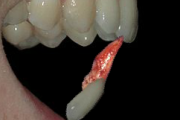

Trauma klassifikatsioon 2 (Mitsuhiro Tsukiboshi,DDS)